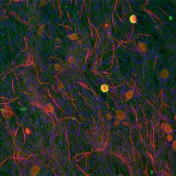

• Fluorescence microscopy image of in vitro model of myelin sheath formation by Schwann cells around neuronal axons.

How does neuropathy happen?

5/16/17

New research on myelination by UB scientists reveals a pathway and a possible therapeutic option.